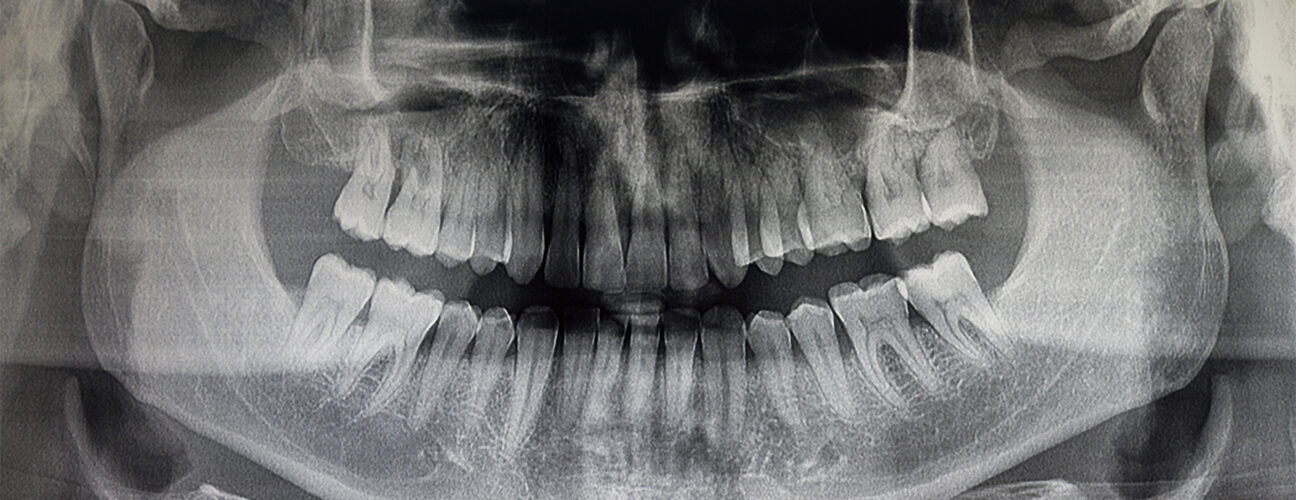

At Portal Dental Pasadena in Pasadena, TX, Panorex technology allows our dental team to capture a full-mouth image in just seconds. This innovative system rotates around your head to create a single, two-dimensional image of your entire oral structure, including the teeth, jaw, and surrounding tissues. Unlike intraoral imaging, which captures small sections of the mouth, this tool provides a complete view, helping dentists evaluate tooth alignment, wisdom teeth placement, and jaw joint function. The efficiency of this system makes it especially valuable for diagnosis and treatment planning in both adult and pediatric dentistry.

For dental professionals at Portal Dental Pasadena, the clarity of the images produced by this tool enhances diagnostic accuracy. It allows for early detection of issues like cysts, tumors, impacted teeth, and bone abnormalities, conditions that may not be visible in standard intraoral imaging. This enhances the level of care and allows for prompt, effective treatment when issues arise. The digital format also enables easy storage and secure sharing with specialists, speeding up referrals and second opinions when needed. If you’re seeking a panoramic X-ray near you, our Pasadena team ensures the imaging process is efficient, informative, and patient-focused.